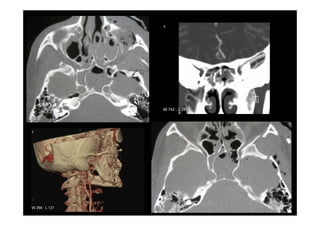

Fracturas complejas de la cara

Fracturas complejes de la cara

Fracturas Cigomáticas Complejas

Fracturas Órbito-craneanas

6 traumatismos faciales